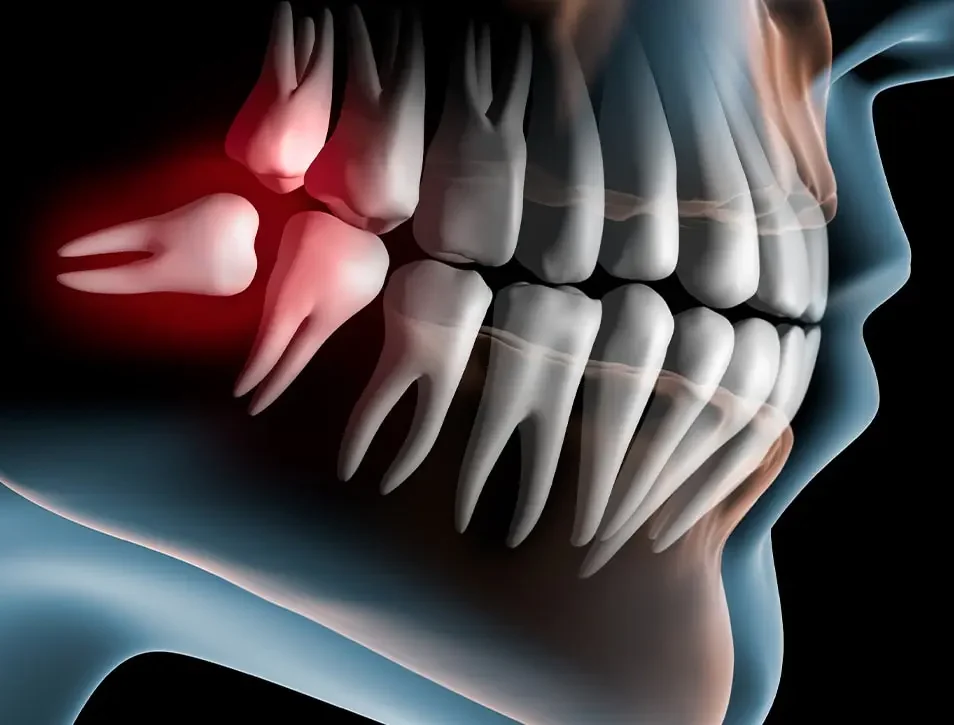

Why wisdom tooth removal is necessary?

When a tooth is extracted, the bone that once surrounded the tooth can begin to resorb (break down) over time. This is particularly common after wisdom teeth removal, especially if the teeth were impacted (not fully erupted) or if the extraction site is large. A bone graft helps fill the empty space left behind, preventing the bone from shrinking or deteriorating. This is important because maintaining the bone density and structure of your jaw helps preserve its shape and functionality.